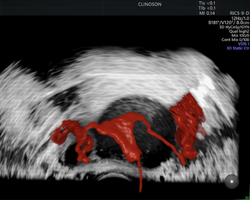

Apaixonado por diagnósticos precisos e tratamentos minimamente invasivos, sou especialista em exames avançados, como a avaliação da endometriose e o HyCoSy (Histerossonografia com Contraste), e também em tratamentos minimamente invasivos de miomas uterinos.

- Pioneiro na realização de HyCoSy – Histerossonossalpingografia com contraste de microbolhas em Porto Alegre